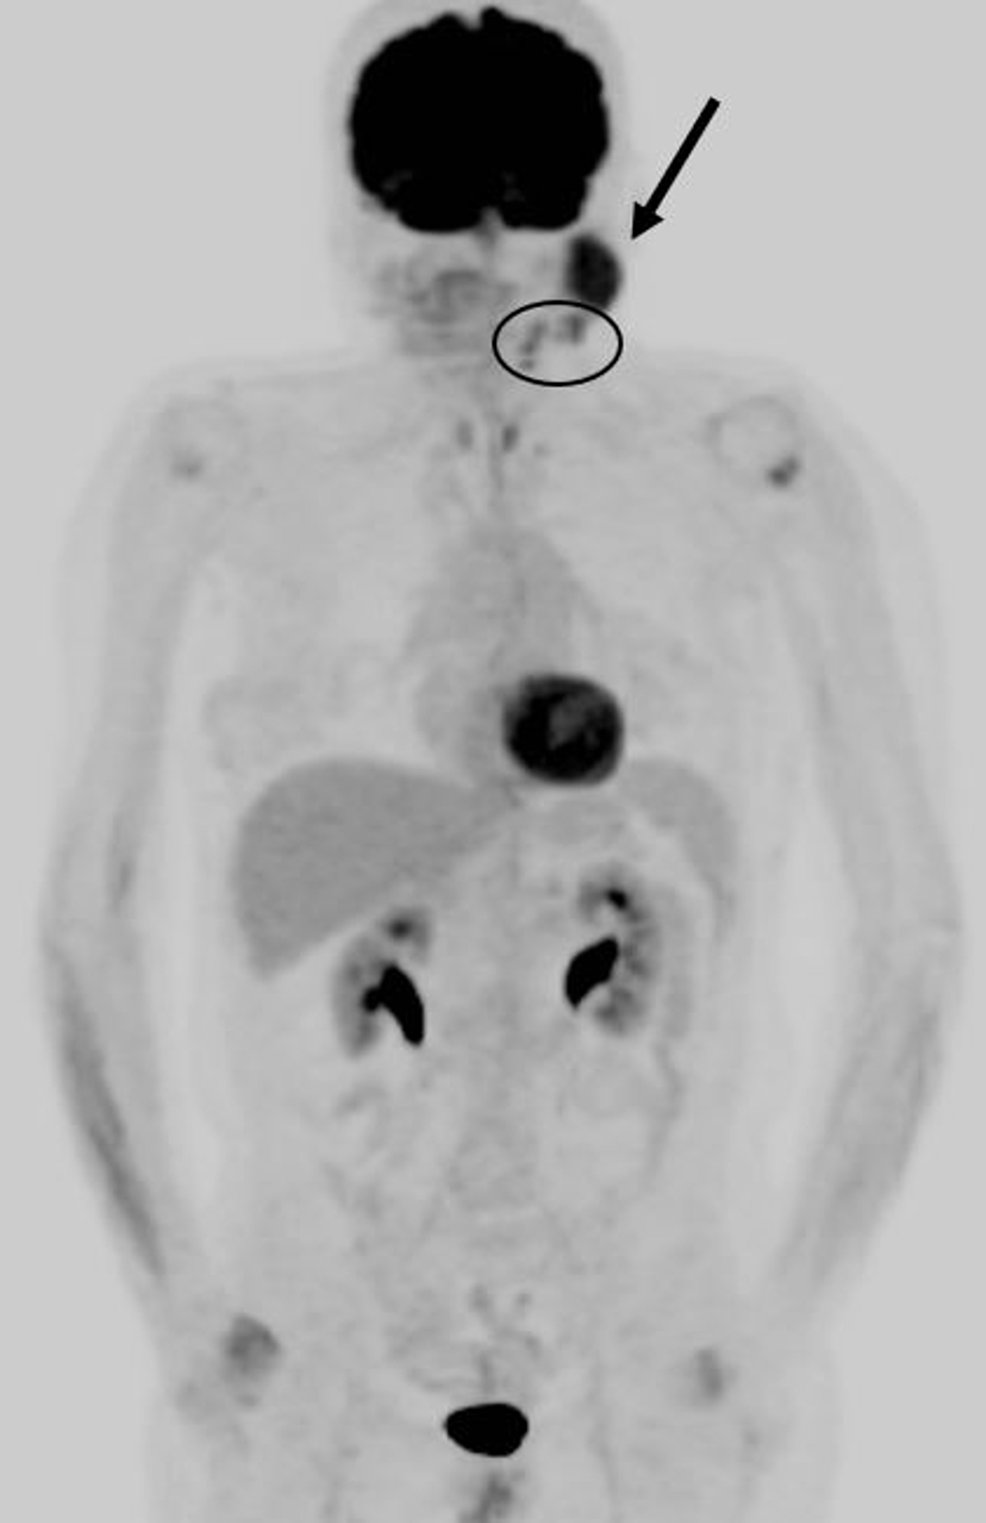

Increased 18FFDG Uptake in Degenerative Disease of the Spine Degenerative Pattern Of Uptake though the reported sensitivity of bone scan is high, its specificity is low due to increased metabolic activity seen in benign disease. indiscriminately classifying shoulder uptake as ‘degenerative changes’ may negatively affect the patient, because. uptake means that the dye is being absorbed by the bone. qualitative scan interpretation using low dose ct for lesion localization. Degenerative Pattern Of Uptake.

Increased 18FFDG Uptake in Degenerative Disease of the Spine Degenerative Pattern Of Uptake indiscriminately classifying shoulder uptake as ‘degenerative changes’ may negatively affect the patient, because. uptake means that the dye is being absorbed by the bone. though the reported sensitivity of bone scan is high, its specificity is low due to increased metabolic activity seen in benign disease. when uptake of 67 ga is greater (compared to surrounding. Degenerative Pattern Of Uptake.